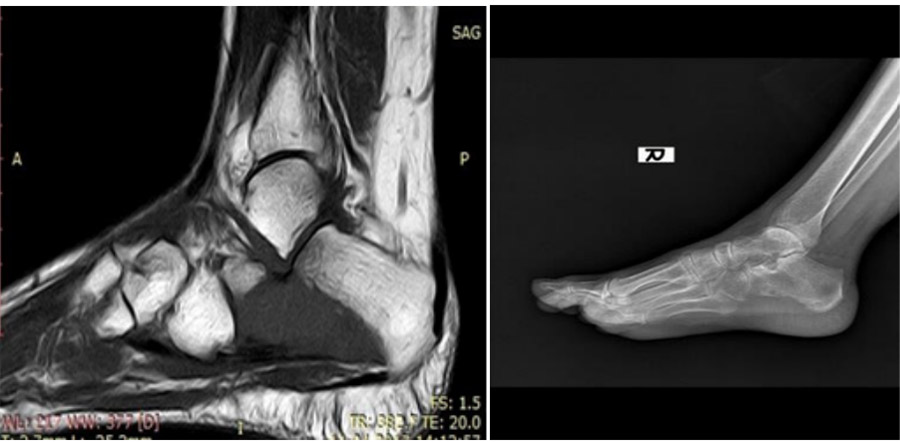

Before the surgery: The X-ray shows degeneration in the right heel bone, and the MRI shows tumor tissue in the same area.